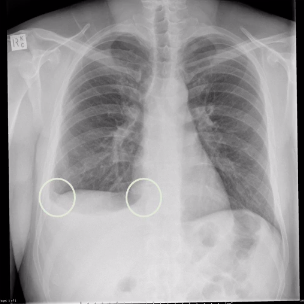

whats wrong here?

blunted cardiophrenic and costophrenic angles